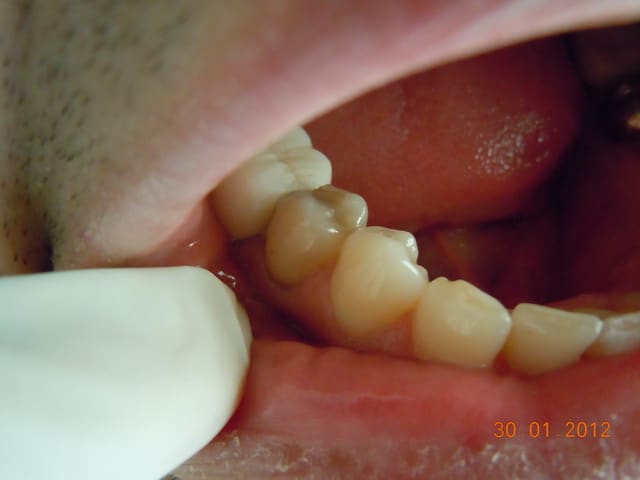

Bonjr! récente recrue sur le forum,jsuis ortho exclu et mon chir dent a proposé à mon homme un IC et une ccm pour sa 45... ça me semble un peu invasif...

-endo RAS bien que vieille

-pan lingual intact et le vestib. quasi

(quand c'est les siens bizarrement on bugue...)

Bon d'ac. dent dévitalisée=fragile=risque de fracture blabla

Perso elle pas belle (noircie) mais c'est la sienne et il est assez couronné comme ça

qu'est ce que vs en pensez? des Idées?

Il aurait fallu une photo en vue occlusale. D'après ce que je vois, un joli composite direct doit être largement suffisant. Les prémolaires du bas sont des dents qui se cassent rarement, surtout s'il n'y a qu'une cavité proximale et non MOD (en plus, largement supragingivale)

Il n'y a pas qq chose de louche au mésial de la 47 ?

et comme ceramik, il y a un truc louche sur 47

Refaire aussi la 47 (reprise de carie) et la 46 qui sont dégueulasses.

Pour la 45, un truc sans tenon (soir un compo direct avant de prendre l'empreinte pour 46, soit un inlay).

Comme Marc, les prémol du bas se fracturent rarement, mais ça arrive quand même...